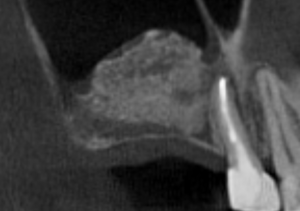

すき間なく緊密に根管充填されている

再感染リスクを抑える垂直加圧方式で充填しています(すき間が生じにくい)